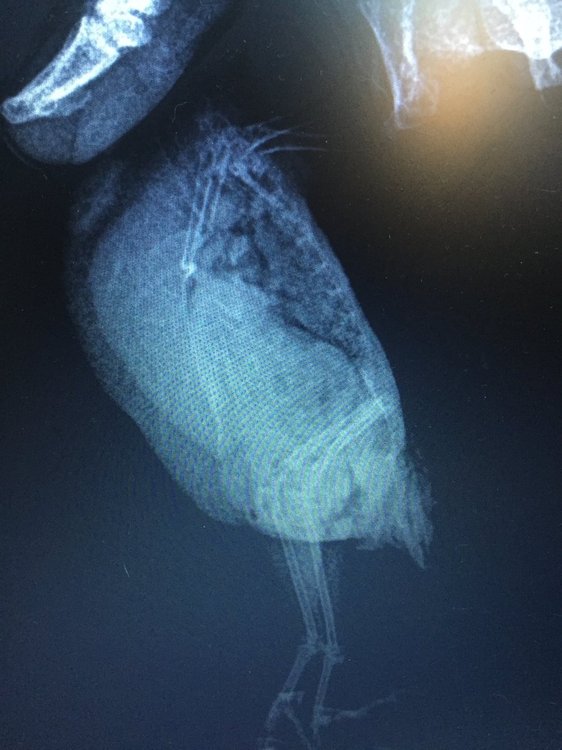

Сделали рентген и анализ помета.

По рентгену (см. приложение) – увеличен живот, печень.

Повторный рентген врач сказала можно сделать, но искать и определять у какого органа опухоль нет смысла, так как на лечение это не повлияет.

Фотографии сегодня сделала, насколько смогла четкие, трогать боюсь, он пищит, вырывается, посмотрите пожалуйста, фото рентгена от 05.06 прилагаю. Что это за опухоль? Чего ждать? Какая должна быть диета? Я сегодня где-то в ветке прочла, что морковь нельзя, а она у нас самая любимая. Из клетки не входит, со мной не общается. Я боюсь вытаскивать его в таком состоянии. Нужно ли его вытаскивать и провоцировать полеты? Как помочь?